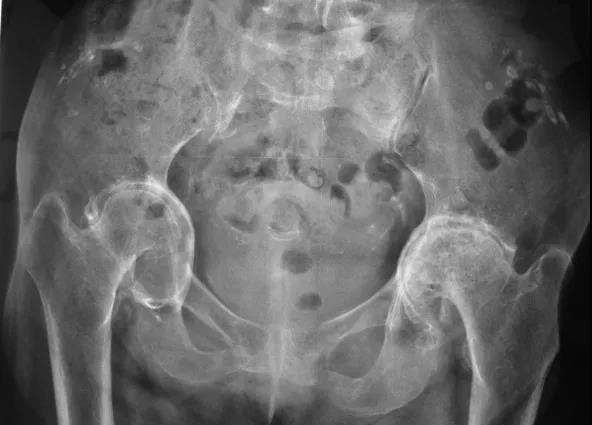

FAI影像学检查前后位片:可见股骨头不同程度的手枪柄样畸形侧位片: 观股骨头颈交界处骨性隆起;CE角﹥40°;髋臼后倾畸形;股骨颈的囊性变

FAI影像学检查CT: 冠状位可见髋臼后倾股骨颈轴位可见头颈交界处骨性隆起α角增大,股骨颈偏心距异常

FAI:齿轮型(cam-type )影像:股骨头、颈间的凹陷不足,可伴局部的骨质增生、硬化、囊变部位:前外股骨头、颈交界区

FAI:螯钳型(pincer-type)横断面显示髋臼后倾尤其是上1/3的后倾